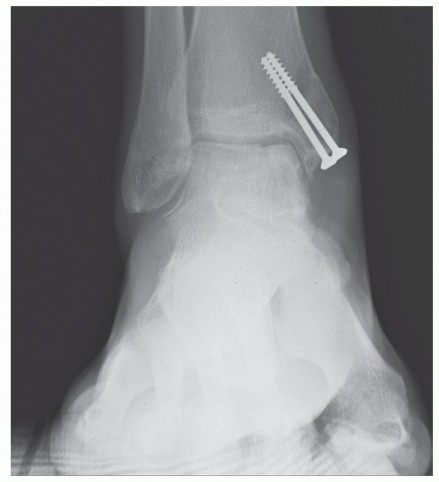

We routinely obtain simulated weight-bearing radiographs at 6 weeks and 10 weeks, and again at 14 to 16 weeks, depending on the progression of healing. If there was a concern about fixation of the graft or osteotomy, then radiographs are also obtained at the first postoperative visit (

FIG 4

).

FIG 4 • Postoperative radiographs. A,B. AP and mortise views showing anatomic reduction of medial malleolar osteotomy. C. Sagittal view.

Knee cartilage has a different thickness than ankle cartilage; therefore, an appropriately placed osteochondral graft from the knee may appear recessed on the postoperative radiograph (

FIG 5

*).